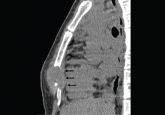

ArticleA 26-year-old woman with a lump in her chestAuthor:Christopher S. King, MDPublish date: March 1, 2012Computed tomography revealed a necrotic mass and bony destruction of the inferior sternum, but no pulmonary parenchymal lesions. What is the most l...Read More